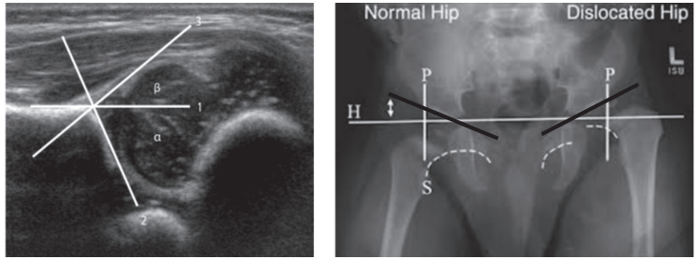

Observe as figuras abaixo:

Fonte: DOI: 10.1007/s43465-021-00539-7

Sobre a DISPLASIADO DESENVOLVIMENTO DO QUADRIL, analise as afirmativas:

I- O diagnóstico imagenológico pode ser realizado por ultrassonografia e RX da pelve em AP.

III- Na ultrassonografia da articulação coxofemoral, a diminuição do ângulo α (alfa) e o aumento do ângulo β (beta) significam que há uma relação anormal da cobertura da cabeça femoral pelos referenciais acetabulares.

IV- Para o reconhecimento radiográfico da luxação congênita do quadril, é traçada uma linha horizontal que passa pelo bordo superior dos acetábulos e outras duas perpendiculares a esta e que passam pelo bordo inferior de cada acetábulo.

V- O índice acetabular, ou ângulo de Kleinberg, formado pela linha de Hilgenreiner e outra que passa pelos bordos superior e inferior de cada acetábulo, está aumentado no quadril displásico e luxado.

VI- Alinha curva imaginária de Shenton, traçada ao longo do bordo externo do colo femoral e bordo superior do ramo isquiopubiano inferior está descontinuada no lado do quadril luxado.

É CORRETO o que se afirma apenas em: